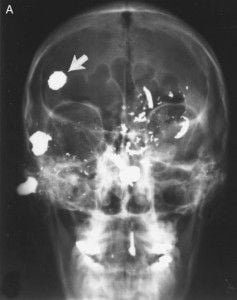

(A) Vista frontal muestra una bala que cubre el seno frontal derecho

(flecha), que era la única bala fácilmente accesible. El resto fueron alojados en el cerebro o los huesos faciales.